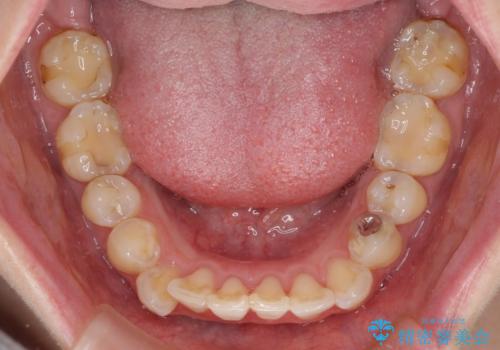

- 出っ歯と口の閉じにくさ、デコボコを気にして来院された患者様です。

口元の突出感を改善するため、上下左右第一小臼歯4本の抜歯を行い、ワイヤー装置による矯正治療を行うこととしました。